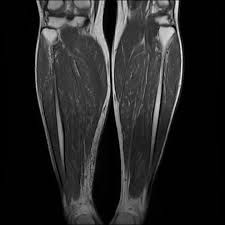

Foot Muscles Mri / Fatty Muscle Atrophy Prevalence In The Hindfoot Muscles On Mr Images Of Asymptomatic Volunteers And Patients With Foot Pain Radiology. Trauma effects of direct injury or tear denervation injury: The aim of this review is to provide the reader with a comprehensive overview of the magnetic resonance imaging (mri) characteristics of the most common benign and malignant soft tissue neoplasms which occur around the foot and ankle. Both muscles are innervated by the deep fibular nerve. Mri is an ideal method for identifying areas of muscle atrophy and fatty infiltration. However, the roles of the extrinsic foot muscles during running have not been adequately identified.

The muscles lie within a flat fascia on the dorsum of the foot (fascia dorsalis pedis) and are innervated by the deep fibular or peroneal nerve. The intrinsic foot muscles comprise four layers of small muscles that have both their origin and insertion attachments within the foot foot muscles mri. Mri is an ideal method for identifying areas of muscle atrophy and fatty infiltration. They are mainly responsible for assisting some of the extrinsic muscles in their actions. Magnetic resonance imaging (mri) is the modality of choice in diagnosing accessory muscles, delineating their relationship to adjacent structures, and differentiating them from soft tissue tumors.

Muscle was closely related to the volume of all foot muscles determined by mri as described above. This imaging technique assesses the ligaments and tendons, neurovascular structures (tarsal tunnel and plantar fascia), and the osseous structures(19). At advanced foot and ankle centers of illinois, we have made this expensive imaging a lot more affordable. Related posts of foot muscle anatomy mri muscle anatomy trivia. Magnetic resonance imaging, otherwise known as mri, uses a combination of magnetic fields and radio waves to take images of the internal structures of your body. Magnetic resonance imaging (mri) is the modality of choice in diagnosing accessory muscles, delineating their relationship to adjacent structures, and differentiating them from soft tissue tumors. Accessory muscles are isointense to skeletal muscle on all pulse sequences, and can insert by fleshy muscular or tendinous insertions. The purpose of this study was to investigate the relationship of muscle mri findings and gait all dm1 patients presenting with foot drop showed high intensity signals. Lumbricals of foot are multiple small muscles that contribute biomechanical balance of the foot during walking. The muscles acting on the foot can be divided into two distinct groups; Mri of the soft tissues of the foot visualizes the fat cushions of the sole, heels, fingers and can show swelling, foci of infiltration and inflammation. Adductor hallucis is anatomically located in the central compartment of foot, but the muscle is functionally grouped with the medial plantar muscles of foot because it acts on the great toe (hallux). An ankle mri also offers a look at the bones of the lower leg that help make up the ankle joint, such as the tibia and fibula, as well as the muscles of the foot.

Role Of Intrinsic Muscle Atrophy In The Etiology Of Claw Toe Deformity In Diabetic Neuropathy May Not Be As Straightforward As Widely Believed Diabetes Care from care.diabetesjournals.org Accessory muscles are isointense to skeletal muscle on all pulse sequences, and can insert by fleshy muscular or tendinous insertions. An ankle mri also offers a look at the bones of the lower leg that help make up the ankle joint, such as the tibia and fibula, as well as the muscles of the foot. Your doctor, with the help of a radiologist, can then examine these images to determine whether there is anything wrong with your foot or ankle. The muscles lie within a flat fascia on the dorsum of the foot (fascia dorsalis pedis) and are innervated by the deep fibular or peroneal nerve. The muscles acting on the foot can be divided into two distinct groups; The purpose of this study was to investigate the relationship of muscle mri findings and gait all dm1 patients presenting with foot drop showed high intensity signals. Mri is an ideal method for identifying areas of muscle atrophy and fatty infiltration. Both muscles are innervated by the deep fibular nerve.

The majority of soft tissue lesions in the foot and ankle are benign. This small, thin muscle is absent in about. Denervation changes in muscles early. Mri is the choice of modality for further imaging the ankle and foot after obtaining initial radiographs. With a muscle injury, for example, mri images often show a bright signal indicating that there is more water in the muscle, which is a sign of injury. The muscles lie within a flat fascia on the dorsum of the foot (fascia dorsalis pedis) and are innervated by the deep fibular or peroneal nerve. The adductor hallucis has two heads: The deformity of the foot with abnormal pressure distribution on the plantar surface coupled with reduced or loss of sensation, makes the foot. Mri is an ideal method for identifying areas of muscle atrophy and fatty infiltration. Accessory muscles are isointense to skeletal muscle on all pulse sequences, and can insert by fleshy muscular or tendinous insertions. In addition, an image of all the muscles of the back and plantar part of the foot, all tendons and tendon ligaments, blood vessels and nerves are obtained. One of the large muscles of the leg, it connects to the heel. Case contributed by dr andrew dixon.

The aim of this review is to provide the reader with a comprehensive overview of the magnetic resonance imaging (mri) characteristics of the most common benign and malignant soft tissue neoplasms which occur around the foot and ankle. Magnetic resonance imaging (mri) is the modality of choice in diagnosing accessory muscles, delineating their relationship to adjacent structures, and differentiating them from soft tissue tumors. They are named extensor digitorum brevis and extensor hallucis brevis. With a muscle injury, for example, mri images often show a bright signal indicating that there is more water in the muscle, which is a sign of injury. The muscles of the dorsum of the foot are a group of two muscles, which together represent the dorsal foot musculature.